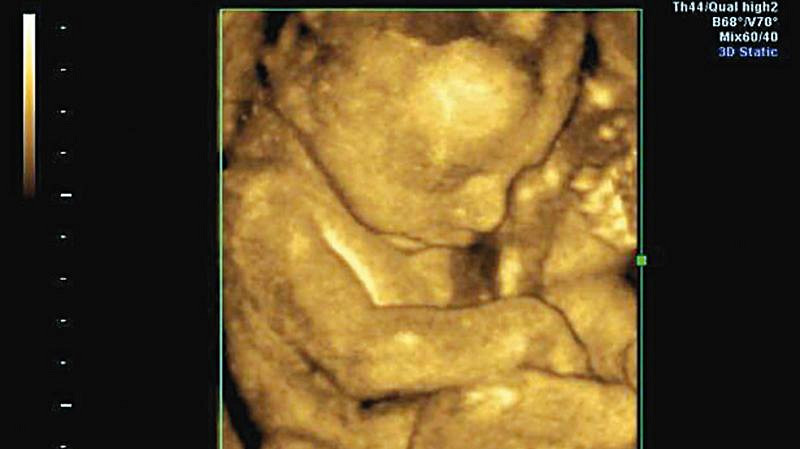

„Te strony powstały dlatego, że kobiety, które chciały się trochę zastanowić przed aborcją, nie miały gdzie zasięgnąć rady, by lepiej zrozumieć, czym jest ciąża. Na stronach proponowanych przez ministerstwo są tylko informacje o aborcji, i to tak sformułowane, jakby to było jedyne wyjście, jakby nie można było zachować dziecka. Strony pro-life podają natomiast dokładne informacje o tym, czym jest aborcja, co to znaczy mieć dziecko, na jaką pomoc może liczyć matka. Na stronach rządowych tego nie znajdziesz. Dlatego strony pro-life wypełniły pewną próżnię. Ponadto warto zwrócić uwagę, że na stronach rządowych w ogóle nie mówi się o dziecku, płodzie, embrionie czy komórkach, lecz o zawartości ciąży. To wprost niewiarygodne, jak daleko można się posunąć” – powiedział Radiu Watykańskiemu redaktor naczelny tygodnika „Famille Chrétienne”.